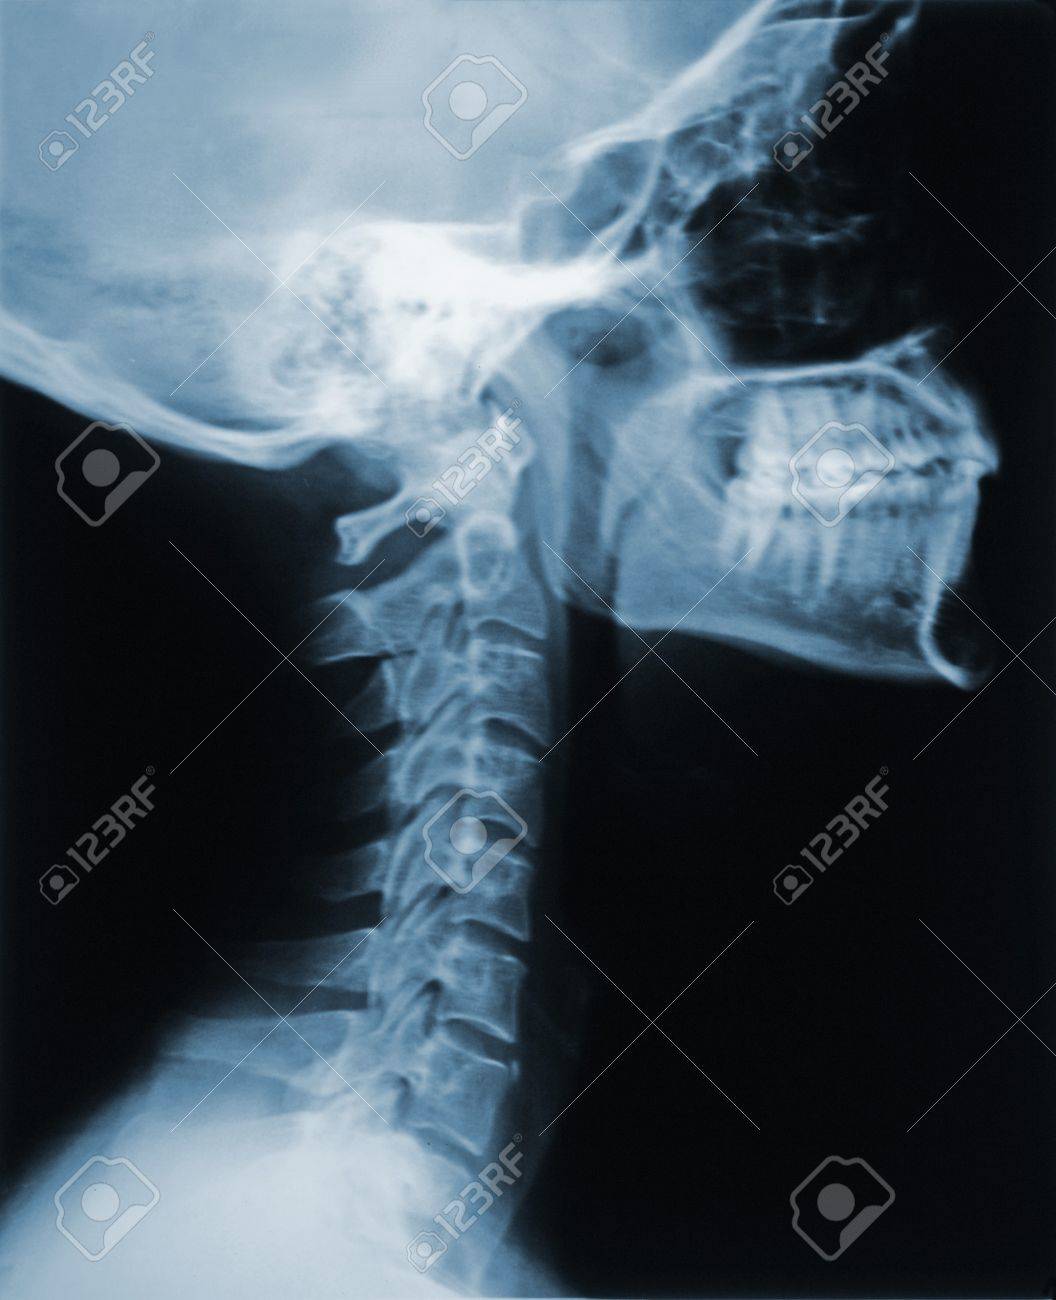

頸椎(首の骨) 頸椎とは 脊椎のくびの部分です. その上に頭蓋骨がつながっています. 脊椎(せぼね)は脊椎動物が全てもっている体を支え る大切なものですが,大きく分けて次の3つの役割が あります. 脊椎(せぼね)の3つの役割 1.体を支える柱. 肺にもやが写る場合に考えられる病気は何があるのでしょうか? May 26, 18 レントゲン肺に白いモヤモヤ レントゲンを撮ると白いモヤが写っており細菌が肺に入ったという説明がありました。 そしてカビなどアレルギー検査もしました。 2日後の今日Dec 04, 06 胸のレドイツの物理学者レントゲンによって発見されたため、レントゲン線といいますが、発見時、正体不明の電磁波だったためxと名づけられました。 肺がん、肺結核、肺炎などの異常があると、白い影として写ります。 高血圧、肥満、首

ストレートネックをレントゲンで見る 僕が参考にしているポイントです 沖縄のストレートネック専門家 肩首こり 首の痛み 緊張型頭痛の整体サロン ラクビヤ

首の骨が逆にカーブしているレントゲン写真 Stock 写真 Adobe Stock

これは 首のレントゲン の写真素材 画像素材 Image